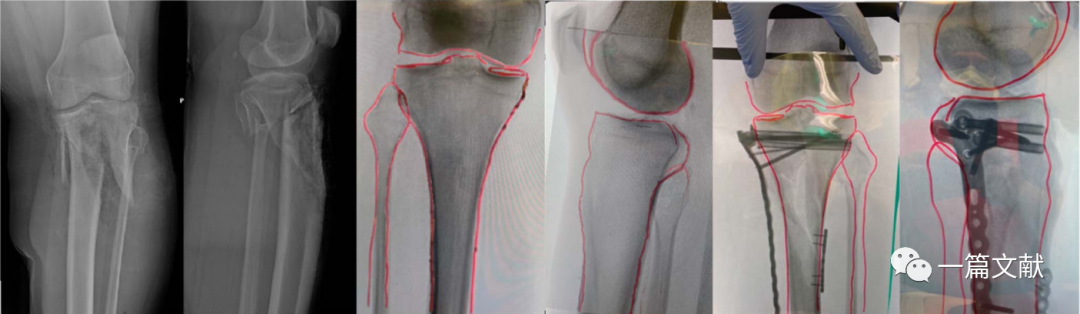

胫骨平台手术

对于累及双侧髁骨折,近端移位明显的骨折尤其有用,如下图: